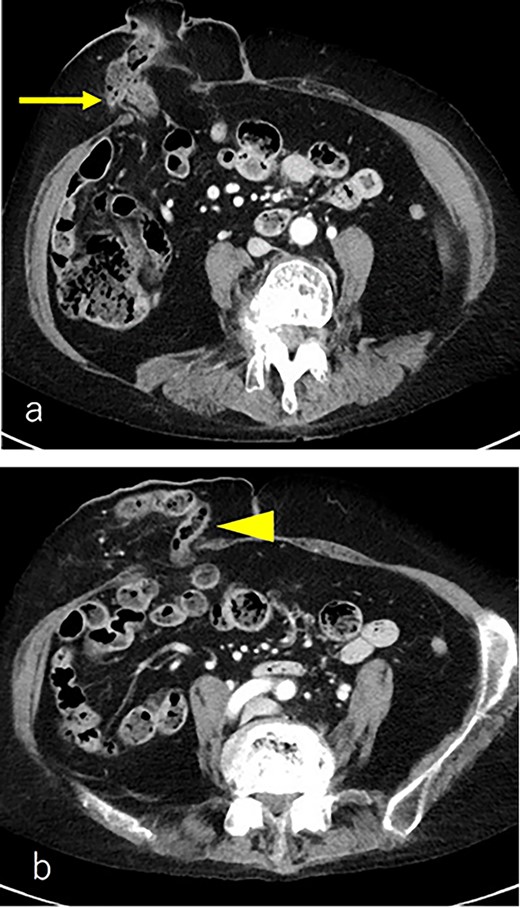

A 75-year-old woman underwent sigmoid colon resection and transverse colostomy for perforation of the diverticulum of the sigmoid colon at 70 years of age at another hospital. The colostomy was performed in the right upper quadrant. She was referred to our hospital with complaints of abdominal discomfort 3 months prior to presentation. She had a history of rheumatoid arthritis and took steroids. Abdominal computed tomography (CT) revealed PSH with loss of fascia around her ostomy. The defect measured ~65 × 60 mm. Herniation of the transverse colon was observed (Fig. 1). No abdominal wall hernia was found, and the diagnosis was European Hernia Society (EHS) type III.

(a) CT scan revealed a prolapse of the transverse colon on the oral side (arrow); (b) CT scan revealed a prolapse of the transverse colon on the anal side (triangle).